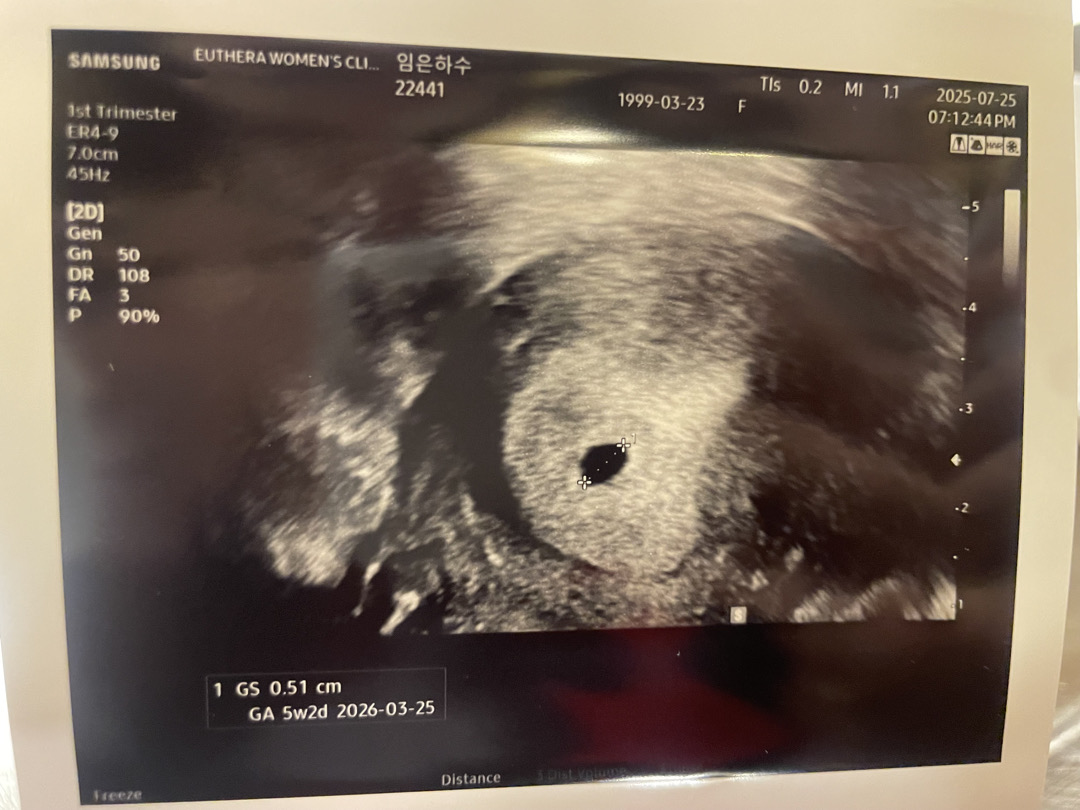

저도 5주차라는 얘기 듣고 오늘 아기집 확인라고왔어요 입덧은 없고 체덧만 있는 상태인데 임신했다는 사실이 안믿기고 아무 생각없다가 막상 아기집 보니깐 얼른 심장소리도 듣고싶어요🥲

5주 1일차인데 입덧은 없고 아직 난황이나 아가는 안보이더라구요! 2주뒤에 오라는데 그때가면 아기랑 심장소리 들을 수 잇을까요?! 2주뒤면 7주차여서요! 그리구 입덧은 보통 언제 시작되나요?! 3주때 입덧 있다가 다시 사라져서요ㅠㅠ

저랑 똑같으세요! 5주1일! 저도 병원에서 2주 뒤에 오면 난황도 보고 심장소리 들을 수 있을 거라고 그 때로 예약해 주셨어요. 입덧은 아직입니다.

저 5주3일차 때 가서 아기집만 보고왔었는데 지난 목요일이 2주 지난 시점이었는데 심장소리 듣고 왔어요!! 저는 입덧은.... 이제 시작된 거 같아요....흑....ㅠㅠ